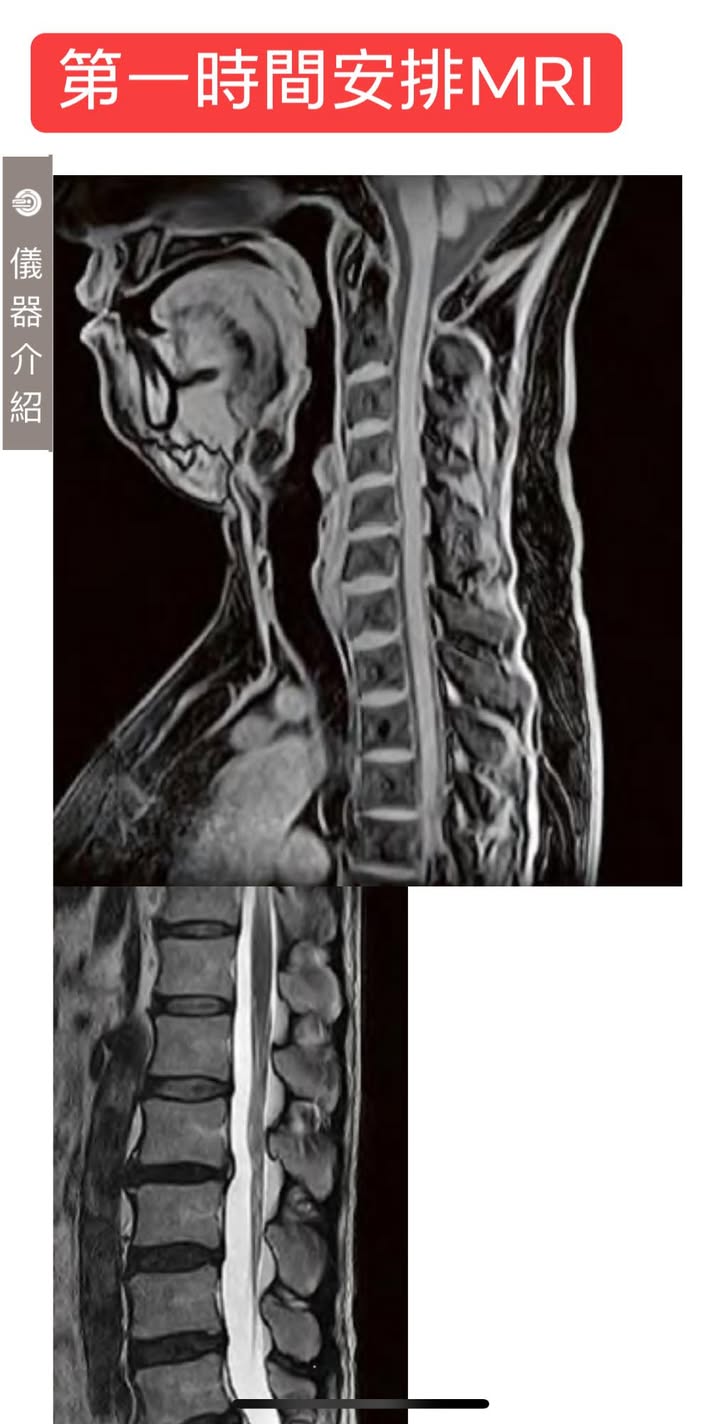

#第一時間安排核磁共振團隊

心得:能夠在第一時間有自己的團隊安排核磁共振在評估上非常重要,核磁共振的費用已超乎想像便宜,台北市跟新北市平均一個部位自費都要8000到12,000,診所跟合作團隊談到五折內搞定,患者曾經問我為什麼那麼便宜,我只是笑笑的說把介紹分紅費用全部回饋給患者了,醫院不用再安排一個影像科醫師約診回來報告,費用自然會降低不少,更重要的是大幅度的減輕患者負擔!